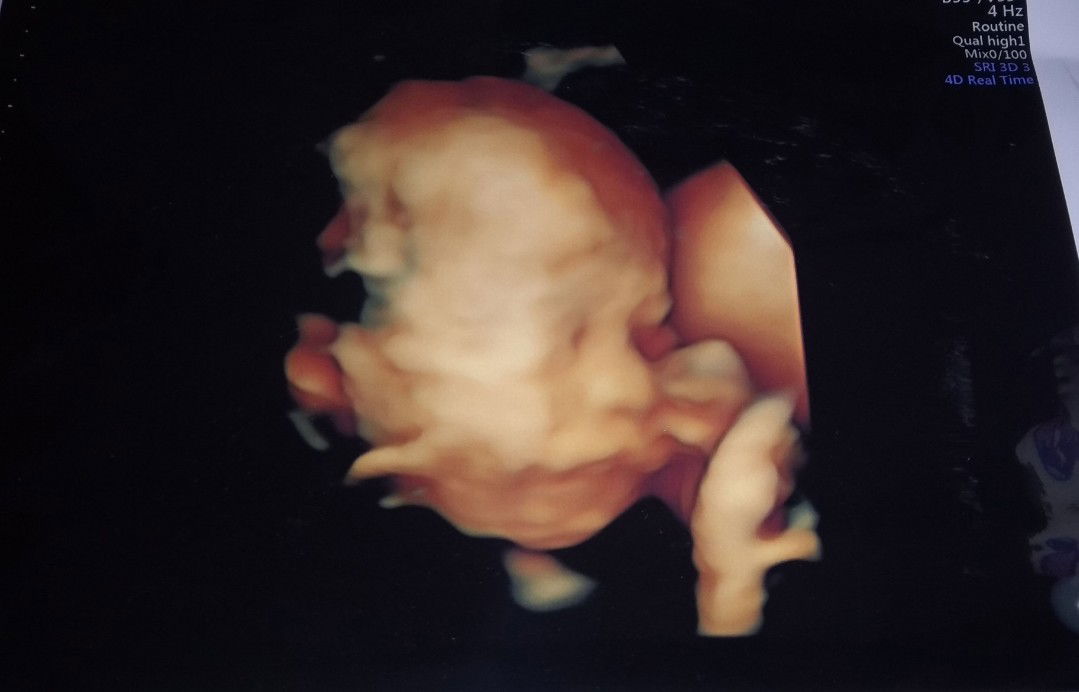

Hasil USG

Ini kehamilanku 6 bulan bun,. Kemarin USG aku yg kedua,. Alhamdulillah dokter bilang sehat dan normal semua. ? semoga calon bayinya bunda disini sehat semua. Amin